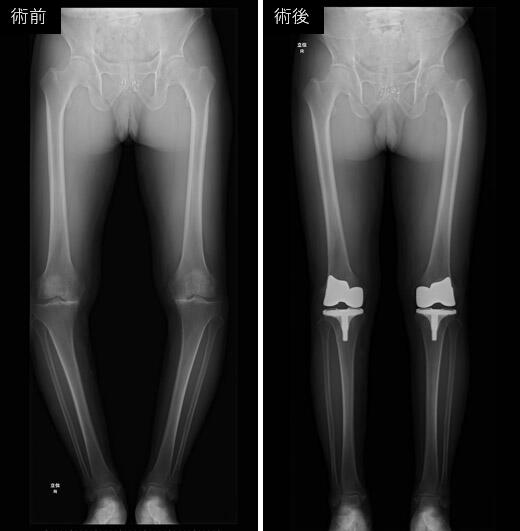

整形外科では、コンピューター支援技術を積極的に活用し、安全性が高く、低侵襲かつ高精度な人工股関節置換術や人工膝関節置換術を実施しています。特に、当院独自に開発した拡張現実(Augmented Reality, AR)技術を取り入れたナビゲーションシステムを導入することで、より正確な手術を実現しています。この技術により、血管や筋肉を詳細に描出することが可能となり、さらなる安全性の向上に貢献しています。また、ロボット支援手術も取り入れており、これら最先端のデジタル技術によって、精密で個別化された医療を提供し、治療成績の向上を目指しています。基礎研究においては、変形性関節症や関節リウマチの病態解明、関節軟骨の修復・変性抑制など、幅広いテーマに取り組み、次世代の医療技術の開発に努めています。